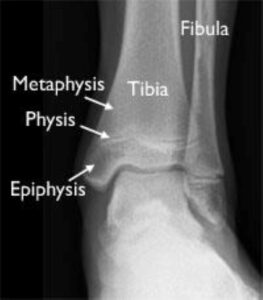

Anatomy of the Ankle Joint

The ankle joint is the point where the tibia (shinbone), fibula (outer ankle bone), and talus (a small bone in the foot) come together. These bones are held in place by ligaments, which function like sturdy ropes, providing stability to the joint by connecting bones and preventing excessive movement. The ankle contains several important ligaments that work together to maintain joint stability and facilitate smooth movement.